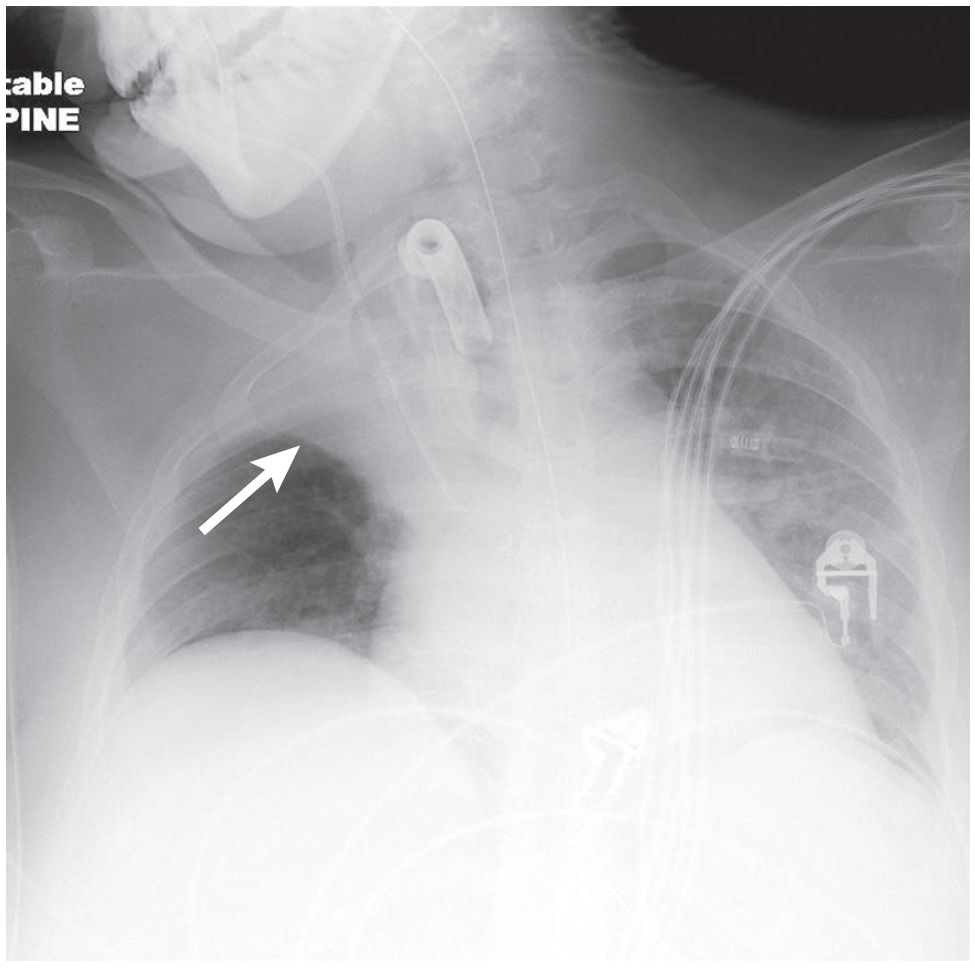

25-year-old woman, status post conversion of pre-existing endotracheal tube to a tracheostomy device, with an abrupt decrease in oxygen saturations and increased work of breathing immediately following the procedure.

What’s the diagnosis ?